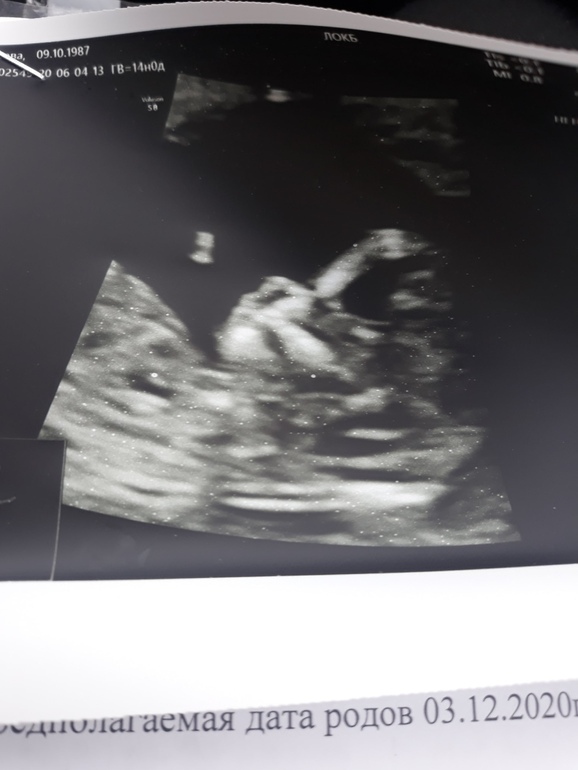

Я очень волновалась, даже документы все оставила дома, ворона, муж срочно подвозил. Но в итоге все хорошо: все прошла и сдала, сказали пороки у вас минимальные🙏 пдр по узи на 10 декабря, по дпм 3 декабря.

Срок по узи 13 недель ровно, по месячным 14 недель, все таки очень поздняя овуляция дала о себе знать, я месячные уже ждала, а у меня оказывается овуляция)

P.s Еще написали хорион по передней стенке, кто когда почувствовал шевеления? Ну и фото, конечно, не очень, не видно ничего и не понятно...обидно, конечно, но думаю все равно еще в 16 недель пойду и увижу своего кроху отчетливее, т.к. экрана у них для мамочек тоже не было(